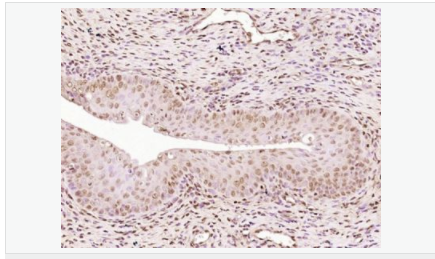

| 英文名稱(chēng) | Progesterone Receptor |

| 中文名稱(chēng) | 孕激素受體抗體 |

| 別 名 | NR3C3; Nuclear receptor subfamily 3 group C member 3; PGR; PR; PRA; PRB; Progesterone receptor; Progestin receptor form A; Progestin receptor form B; PRGR_HUMAN; Progestin receptor form A; Progestin receptor form B. |

| 研究領(lǐng)域 | 腫瘤 免疫學(xué) 信號轉導 生長(cháng)因子和激素 腫瘤細胞生物標志物 |

| 產(chǎn)品應用 | WB=1:500-2000 IHC-P=1:100-500 IHC-F=1:100-500 Flow-Cyt=1ug/Test ICC=1:100-500 IF=1:100-500 (石蠟切片需做抗原修復) not yet tested in other applications. optimal dilutions/concentrations should be determined by the end user. |

| 細胞定位 | 細胞核 細胞漿 |

| 產(chǎn)品介紹 | Estrogen and progesterone receptor are members of a family of transcription factors that are regulated by the binding of their cognate ligands. The interaction of hormone-bound estrogen receptors with estrogen responsive elements(EREs) alters transcription of ERE-containing genes. The carboxy terminal region of the estrgen receptor contains the ligand binding domain, the amino terminus serves as the transactivation domain, and the DNA binding domain is centrally located. Two forms of estrogen receptor have been identified, ER alpha and ER beta. ER alpha and ER beta have been shown to be differentially activated by various ligands. The biological response to progesterone is mediated by two distinct forms of the human progesterone receptor (hPR-Aand hPR-B), which arise from alternative splicing. In most cells, hPR-B functions as a transcriptional activator of progesterone-responsive gene, whereas hPR-A function as a transcriptional inhibitor of all steroid hormone receptors. Function: The steroid hormones and their receptors are involved in the regulation of eukaryotic gene expression and affect cellular proliferation and differentiation in target tissues. Progesterone receptor isoform B (PRB) is involved activation of c-SRC/MAPK signaling on hormone stimulation. Isoform A is inactive in stimulating c-Src/MAPK signaling on hormone stimulation. Subunit: Interacts with SMARD1 and UNC45A. Interacts with CUEDC2; the interaction promotes ubiquitination, decreases sumoylation, and repesses transcriptional activity. Interacts with PIAS3; the interaction promotes sumoylation of PR in a hormone-dependent manner, inhibits DNA-binding, and alters nuclear export. Interacts with SP1; the interaction requires ligand-induced phosphorylation on Ser-345 by ERK1/2 MAPK. Interacts with PRMT2. Subcellular Location: Nucleus. Cytoplasm. Note=Nucleoplasmic shuttling is both homone- and cell cycle-dependent. On hormone stimulation, retained in the cytoplasm in the G(1) and G(2)/M phases. Isoform A: Nucleus. Cytoplasm. Note=Mainly nuclear. Post-translational modifications: Phosphorylated on multiple serine sites. Several of these sites are hormone-dependent. Phosphorylation on Ser-294 occurs preferentially on isoform B, is highly hormone-dependent and modulates ubiquitination and sumoylation on Lys-388. Phosphorylation on Ser-102 and Ser-345 also requires induction by hormone. Basal phosphorylation on Ser-81, Ser-162, Ser-190 and Ser-400 is increased in response to progesterone and can be phosphorylated in vitro by the CDK2-A1 complex. Increased levels of phosphorylation on Ser-400 also in the presence of EGF, heregulin, IGF, PMA and FBS. Phosphorylation at this site by CDK2 is ligand-independent, and increases nuclear translocation and transcriptional activity. Phosphorylation at Ser-162 and Ser-294, but not at Ser-190, is impaired during the G(2)/M phase of the cell cycle. Phosphorylation on Ser-345 by ERK1/2 MAPK is required for interaction with SP1. Sumoylation is hormone-dependent and represses transcriptional activity. Sumoylation on all three sites is enhanced by PIAS3. Desumoylated by SENP1. Sumoylation on Lys-388, the main site of sumoylation, is repressed by ubiquitination on the same site, and modulated by phosphorylation at Ser-294. Similarity: Belongs to the nuclear hormone receptor family. NR3 subfamily. Contains 1 nuclear receptor DNA-binding domain. SWISS: P06401 Gene ID: 5241 Database links: Entrez Gene: 5241 Human Entrez Gene: 18667 Mouse Entrez Gene: 100009094 Rabbit Omim: 607311 Human SwissProt: P06401 Human SwissProt: Q00175 Mouse SwissProt: P06186 Rabbit Unigene: 2905 Human Unigene: 32405 Human Unigene: 742403 Human Unigene: 12798 Mouse Unigene: 437703 Mouse Unigene: 1947 Rabbit Unigene: 10303 Rat Important Note: This product as supplied is intended for research use only, not for use in human, therapeutic or diagnostic applications. |